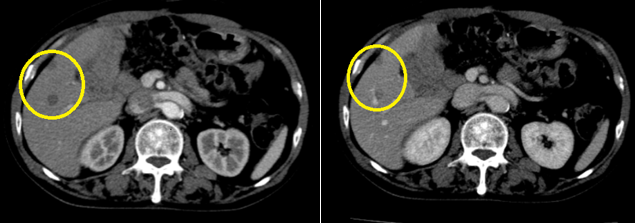

Hình ảnh chụp cắt lớp vi tính ổ bụng sau 3 chu kỳ điều trị hóa chất:

Hình 2: Hình ảnh chụp cắt lớp vi tính ổ bụng: Các nốt ở gan phải, ngấm thuốc kém thì động mạch, tĩnh mạch, kích thước lớn nhất 10x11mm (vòng tròn màu vàng)

Hình ảnh chụp cắt lớp vi tính ổ bụng sau 6 chu kỳ điều trị hóa chất:

Hình 3: Hình ảnh chụp cắt lớp vi tính ổ bụng: không thấy hình ảnh tổn thương trong nhu mô gan

Nhận xét: trước điều trị hóa chất xuất hiện các nốt ở gan ngấm thuốc viền thì động mạch, tuy nhiên sau điều trị hóa chất 6 chu kỳ, không thấy hình ảnh các nốt ở gan.